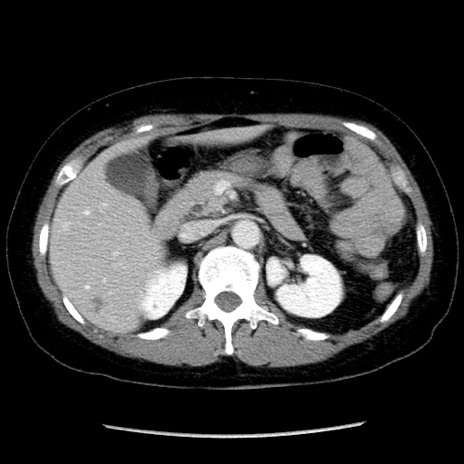

症例6(横断像)

【症例】50歳代女性

【主訴】下腹部痛

【現病歴】本日朝より下痢2回あり。 昼食を食べた後、嘔吐3回、下腹部痛認め、症状軽快せず、当院救急搬送。

【既往歴】卵巣癌術後(8年前に当院で卵巣摘出)

【身体所見】 意識清明、腹部:平坦、腸蠕動音→、やや硬、下腹部自発痛・圧痛あり、反跳痛あり、筋性防御なし。

【データ】WBC 16000、CRP 0.01